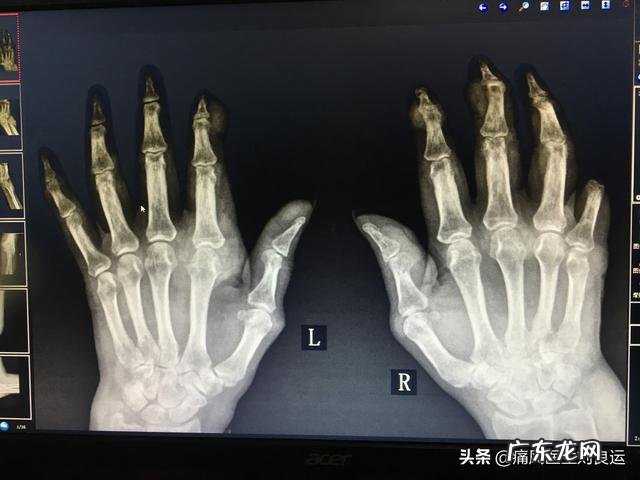

痛风石的病理:痛风石本质是异物性肉芽肿,沉积在组织中的单钠尿酸盐(MSUM)晶体作为异物不容易被消除,因此对组织的刺激长期存在,形成慢性轻度的炎症反应 。痛风石的核心部分为一定量的单钠尿酸盐晶体,围绕着无定形的蛋白质基质,呈放射状排列 。核心周围有单核-巨噬细胞以及上皮样细胞、多核巨细胞浸润,外边有纤维结缔组织包绕,形成境界清除的结节状病灶 。痛风石也可以是多核心的,其间有透明的结晶间质,且含有蛋白质、脂肪和多糖成分 。痛风的大小不一,直径从数毫米到数厘米不等 。随着病情进展,单钠尿酸盐晶体不断沉积,结节肿病灶不断增大,甚至形成巨大痛风石 。痛风石的部位:几乎人体所有组织都可有尿酸盐沉积,唯有中枢神经系统例外 。痛风石尤其喜欢出现在人体的关节内和关节周围的组织,在关节附近的骨骼、和关节附近的滑囊膜、腱鞘与软骨内,侵入骨质形成骨骼畸形,或使骨质遭受损毁,如关节软骨、滑膜、骨骼、肌腱、韧带、关节囊等部位 。人体四肢的远端小关节是痛风石最为“青睐”的地方,像跖趾关节、踝关节、足背、手指关节、掌指关节、腕关节和手背等;人体耳廓上的软骨也是痛风石的首选“居住地”,四肢较大的关节部位,如膝关节、肘关节,则可算的上痛风石的“宜居环境” 。痛风石有时也会出现于典软骨、睑板软骨、角膜和巩膜等部位 。甚至在大动脉、心肌、主动脉瓣、二尖瓣、三尖瓣、舌、会厌、声带和钓状软骨、气管软骨、阴茎、包皮上也会出现痛风石 。而躯干部位如胸、腹、背、腰、臀、肩和四肢的上臂和大腿部位,痛风石则相对比较少见 。肝脏、胆囊、胆道和胰腺等处罕见 。曾有报道在唾液中找到尿酸盐结晶 。脑、脾、肺未见痛风石 。人体的内脏也可发生痛风石,主要见于肾脏实质 。有时可见于输尿管和膀胧 。也最常受累的系统是泌尿系统(如肾脏、输尿管和膀胱),毕竟这是尿酸的出口部位,容易出现尿酸的沉积,另外,胆囊也是比较常见的痛风石部位 。事实上,除了中枢神经系统由于受到血脑屏障的保护,所处的环境里的尿酸浓度远低于其他部位以外,人体几乎所有的组织都可能出现痛风石 。痛风石的临床表现痛风石大小不一,小如芝麻、大如鸡蛋 。痛风患者如果在早期发现小的痛风石时,能积极zhi疗,使血清尿酸浓度长期处于正常范围内,痛风石有望消散 。这是因为痛风石形成的时间尚短,没“修炼”成“不化之身”,里面沉积的尿酸盐还能与血液的成分自由交换,痛风石处于可溶解的时期,但此时痛风石可不断向外周循环释放尿酸盐,又导致血尿酸控制困难 。